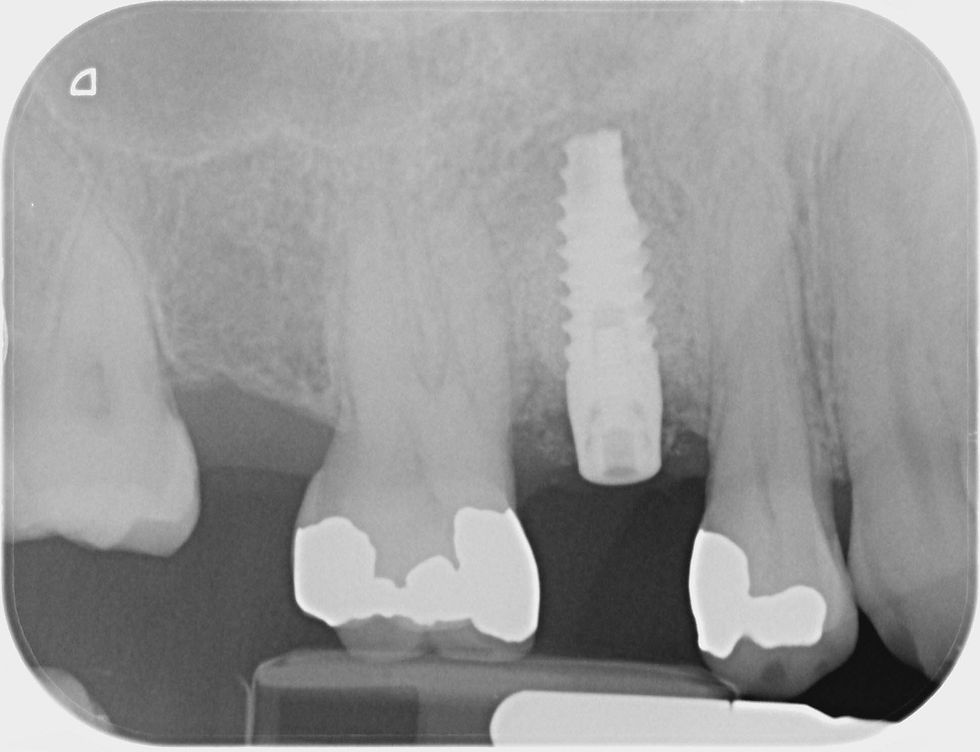

Post-surgical radiograph to verify the correct insertion of the Prama implant.

Radiographic after 7 months from the regeneration: the radiographic examination shows adequate bone volume; the healing of the soft tissue is completed. Therefore, we decide to proceed with the second step of the surgery.